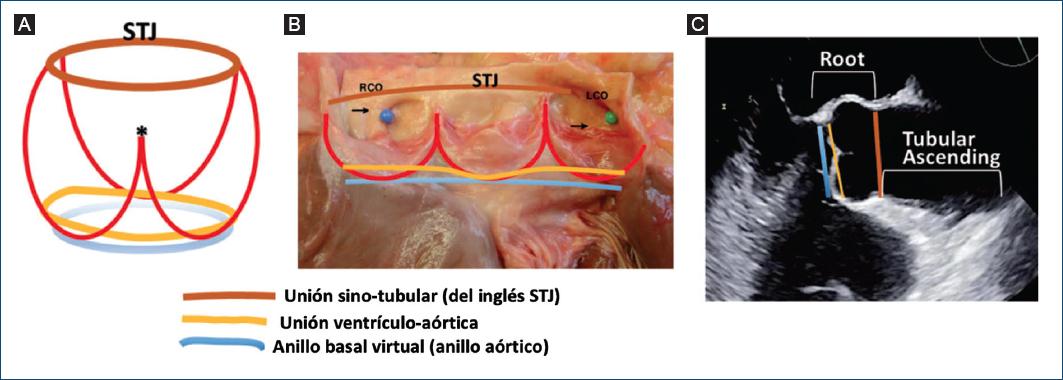

Figura 3 El complejo de la raíz aórtica. A: dibujo esquemático de la raíz aórtica. La línea azul indica el anillo basal virtual (anillo aórtico); la línea amarilla representa la unión ventrículo-aórtica (cuya naturaleza no plana se enfatiza esquemáticamente)30; las líneas rojas muestran las uniones en forma de corona de las cúspides a la pared de los senos aórticos (nótese la diferente altura de la comisura subdesarrollada (asterisco) debajo del rafé en comparación con las otras dos comisuras verdaderas), y la línea marrón representa la STJ. B: todos los límites y estructuras anteriores se muestran (los mismos colores que los anteriores) en una pieza anatómica de una raíz aórtica normal y una válvula aórtica tricúspide. C: vista ecocardiográfica de la raíz aórtica. Se muestran los niveles del anillo aórtico, la unión ventrículo-aórtica y la STJ (mismos colores que los anteriores). Es importante reconocer que es la medición de los diámetros del anillo virtual, los senos y la STJ lo que tiene implicaciones clínicas y prácticas para el paciente con VAB. LCO: orificio coronario izquierdo (alfiler verde y flecha); RCO: orificio coronario derecho (alfiler azul y flecha); STJ: unión sinotubular; VAB: válvula aórtica bicúspide.

Complejo de la raíz aórtica

Aunque «aorta ascendente» y «raíz aórtica» a veces se usan indistintamente para indicar todo el segmento vascular desde la válvula aórtica hasta el origen de la arteria braquiocefálica (comienzo del arco), el término raíz aórtica se refiere solo a la parte más proximal de la aorta torácica ascendente, desde el extremo distal del tracto de salida del ventrículo izquierdo hasta la unión sinotubular (STJ), formada por los senos de Valsalva y que contiene la válvula aórtica29 (Fig. 3). La anatomía y fisiología del complejo de la raíz aórtica y su interacción con la válvula se han investigado a fondo a medida que se han introducido técnicas contemporáneas para la reparación de la válvula aórtica y se han adoptado más ampliamente30,31. Funcionalmente, y particularmente en relación con la competencia de la VAB y la reparación quirúrgica, tres elementos forman el complejo de la raíz aórtica y cooperan para determinar de la dinámica fisiológica de la válvula32: a) la STJ; b) los senos aórticos (de Valsalva) con la línea de inserción de las cúspides en forma de corona en la pared aórtica (que, como se mencionó, asume una forma peculiar en la VAB fusionada, con una de las tres «puntas de la corona» correspondiendo a la pseudocomisura debajo del rafé, alcanzando una altura más baja que las otras dos (Fig. 3), y c) el anillo aórtico, que es una línea circular virtual dentro del tracto de salida del ventrículo izquierdo, que atraviesa el nadir de las cúspides aórticas y las bases de los respectivos triángulos intercúspides (Fig. 3). El anillo aórtico es un sustituto virtual de la unión ventrículo-aórtica, que es el verdadero límite del complejo de la raíz aórtica, identificado anatómicamente como la transición del músculo ventricular a la media aórtica y situado circunferencialmente ligeramente por encima del nadir de las cúspides aórticas, cruzando las líneas semilunares de la inserción de cada cúspide (Fig. 3). Sin embargo, tanto para fines quirúrgicos como de imagen, el anillo aórtico virtual es el punto de referencia anatómico práctico y clínicamente utilizado que constituye el tercer componente del complejo de la raíz aórtica, como se describió anteriormente. El complejo de la raíz aórtica, particularmente el tamaño del anillo aórtico y la STJ, son indispensables para proporcionar suficiente área de coaptación diastólica de las cúspides y prevenir la progresión de la regurgitación aórtica33 y su recurrencia después de la cirugía34. Por lo tanto, el complejo de la raíz aórtica es el andamio anatómico que mantiene la competencia de la VAB, con las cúspides de la VAB actuando como una válvula sin stent y el complejo de la raíz aórtica como su stent nativo32.